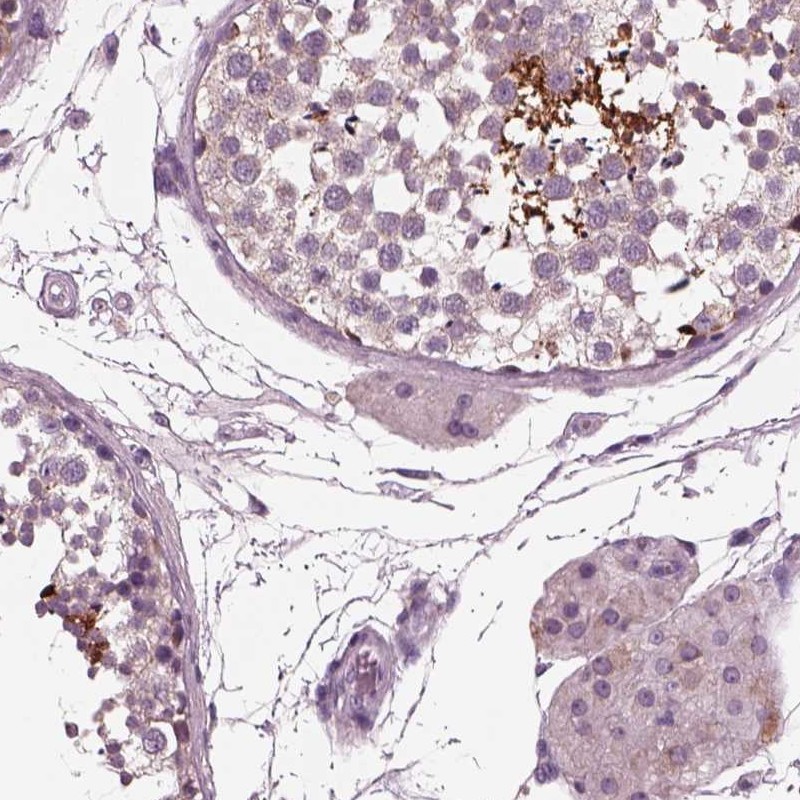

Immunohistochemical staining of human testis shows strong cytoplasmic positivity in cells in seminiferous ducts.